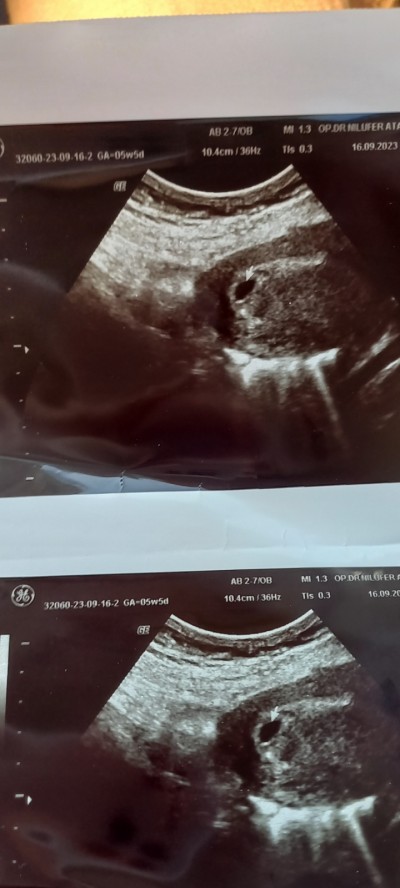

Sorum yukrda 5+1 gitim bebek var kese var kalp atışı ne zmn olur progesteron verdi

Gebelik haftası 5+1

Ben de özele gidiyorum normal usgde keseyi gördüm kese düzgün ve dış gebelik değil dedi 2 hafta sonra kalp atışı için çağırdı. Ilk kızımda da 5 haftalikken gitmistim o zamna vajinal usg basılmıştı yine sadece keseydi o yüzden merak ettim. Bakın ben de foto ekledim bu şekilde göründü